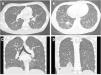

Se describe el caso de un adolescente de 17 años que ingresa por insuficiencia respiratoria aguda grave junto con hipoxemia. Durante su estancia se realizaron numerosas pruebas complementarias siendo los hallazgos en la tomografía computarizada pulmonar imprescindibles para el diagnóstico; en ella se aprecian micronódulos en vidrio deslustrado con patrón de árbol en brote de distribución difusa1 (fig. 1).

Imágenes de tomografía computarizada durante su ingreso. Las imágenes axiales (A y B) y coronales (C y D) muestran pequeñas opacidades micronodulares con patrón de árbol en brote distribuidos de forma difusa, con región subpleural respetada. En las imágenes B y D se evidencian focos consolidativos en LID.